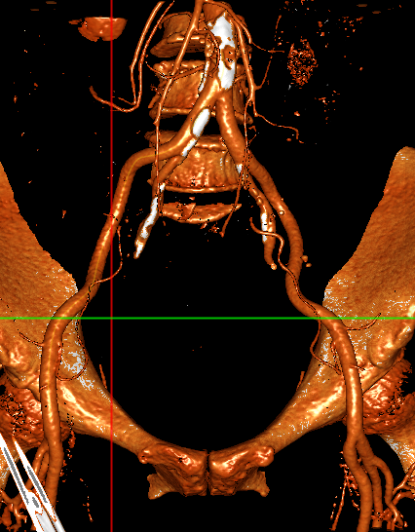

主动脉CT

主动脉瓣环平均直径:22.4mm

左室流出道平均直径:23.2

左冠脉开口:10mm

右冠脉开口高度:14.7mm

患者为功能性二叶瓣,左右瓣叶融合,左冠脉开口低,窦部大,冠脉风险低。

袁义强院长总结了该病例特点:功能性二叶瓣主动脉瓣狭窄,患者有心衰症状,解剖适合TAVR,年龄66岁,存在明确TAVR手术适应症。选择右股动脉入路,根据CT测量分析选择瓣膜大小,窦部情况可,瓣环平均直径22.4mm,选择植入24mm瓣膜。